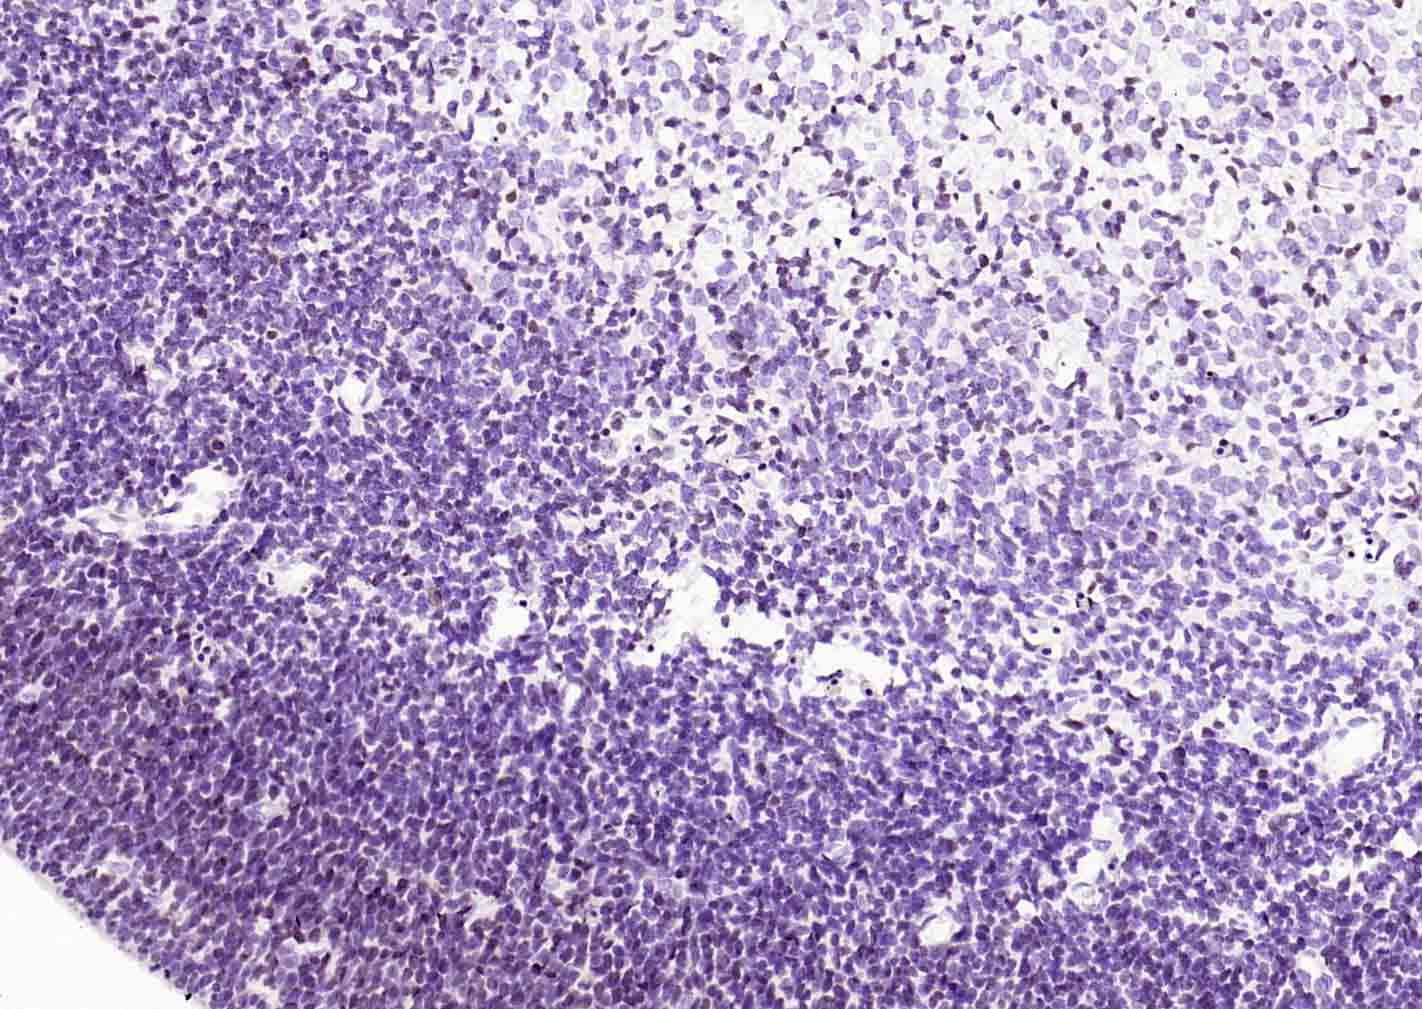

Paraformaldehyde-fixed, paraffin embedded Human Esophagus Cancer; Antigen retrieval by boiling in sodium citrate buffer (pH6.0) for 15 min; Antibody incubation with SOX2 Monoclonal Antibody, Unconjugated(bsm-60788R) at 1:300 overnight at 4°C, followed by conjugation to the SP Kit (Rabbit, SP-0023) and DAB (C-0010) staining.